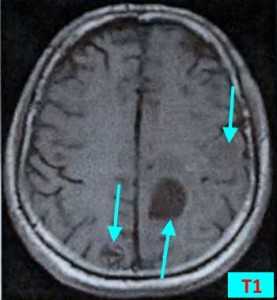

МРТ-признаки метастазов в мозг

МРТ — более чувствительный и специфичный метод в выявлении метастазов ЦНС по сравнению с компьютерной томографией. Вторичные опухоли имеют ряд общих черт при МР-исследовании.

Т1 ВИ (без контрастного усиления)

- Изоинтенсивный либо умеренно гипоинтенсивный сигнал по отношению к белому веществу мозга от активной части опухоли

- Гипоинтенсивный сигнал от центральной зоны (некроза и распада)

Т2 ВИ

- Гиперинтенсивный сигнал от центрального участка метастаза

- Повышение интенсивности сигнала от отечных тканей мозга, окружающих вторичную опухоль, вследствие чего метастазы становятся более четкими на изображениях

МРТ с контрастным усилением

- Выраженное увеличение интенсивности сигнала

- Усиление сигнала по периферии в виде «кольца» или «короны»

- Помогает дифференцировать кровоизлияиния в метастаз от геморрагического инсульта (выраженное усиление сигнала на Т1 ВИ)

Метастазы головного мозга на МРТ. Фото. Определяются множественные метастазы в мозг при раке легкого: слева в режиме Т1-ВИ в виде гипоинтенсивных образований, справа — в режиме Т2-ВИ виде множественных участков повышенного сигнала, окруженных зоной перифокального отека. У пациента подтверждена первичная опухоль легкого.